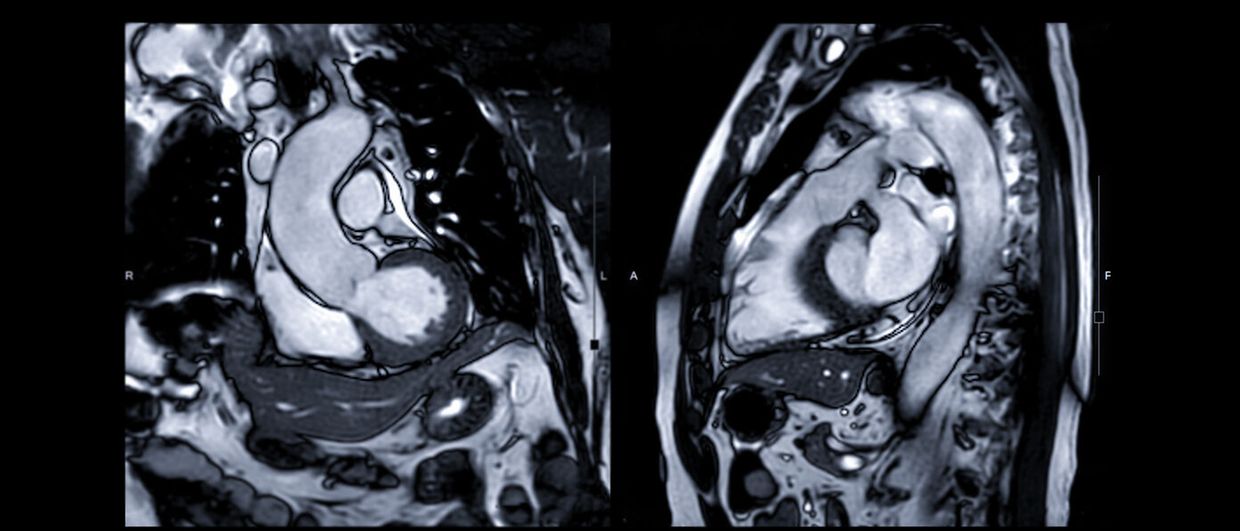

Sie kennen die Stärken und Schwächen der kardialen Magnetresonanztomografie (MRT) in der Diagnostik seltener hypertropher Kardiomyopathien, sowie deren Möglichkeiten in der Gewebecharakterisierung und zur Verlaufskontrolle.